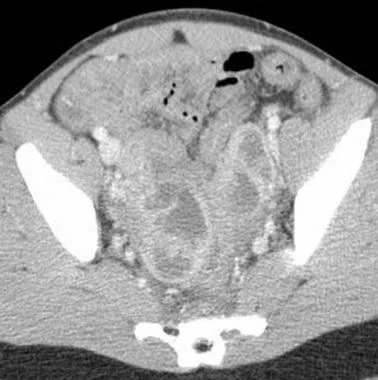

尽管大多数TOAs都是通过超声诊断的,但是在引流之前进行诊断性的CT是很有帮助的,这样可以评价脓肿或多个脓肿的整体范围,并且排除更适合进行手术的弥漫腹膜病变。

如果脓肿发生了机化,即使有多个脓肿,也可以经皮引流。可以通过经腹腔,经臀,或经阴道路径来进行穿刺,取决于脓肿的位置。CT用于经臀路径中,并且也常常用于经腹路径中,但如果选择了经阴道入路,就应该用经阴道超声进行引导。可以使用市售或定做的活检导引器来插入针头。

有人建议,对于直径大于7cm的脓肿,最好联合抗生素和PAD作为初始治疗,但较小的脓肿只是在内科治疗无效时需要进行引流。直径小于3-4cm的脓肿可以进行抽吸,但往往无法插管,尽管单纯的细针穿刺就可能起到治疗作用。抽吸、引流和手术的具体作用以及时间安排还有待进一步阐明。PAD有可能降低同大型手术相关的早期致病率和死亡率,能够降低住院治疗的费用,并且能够避免对年轻女性进行手术绝育以及提前绝经。